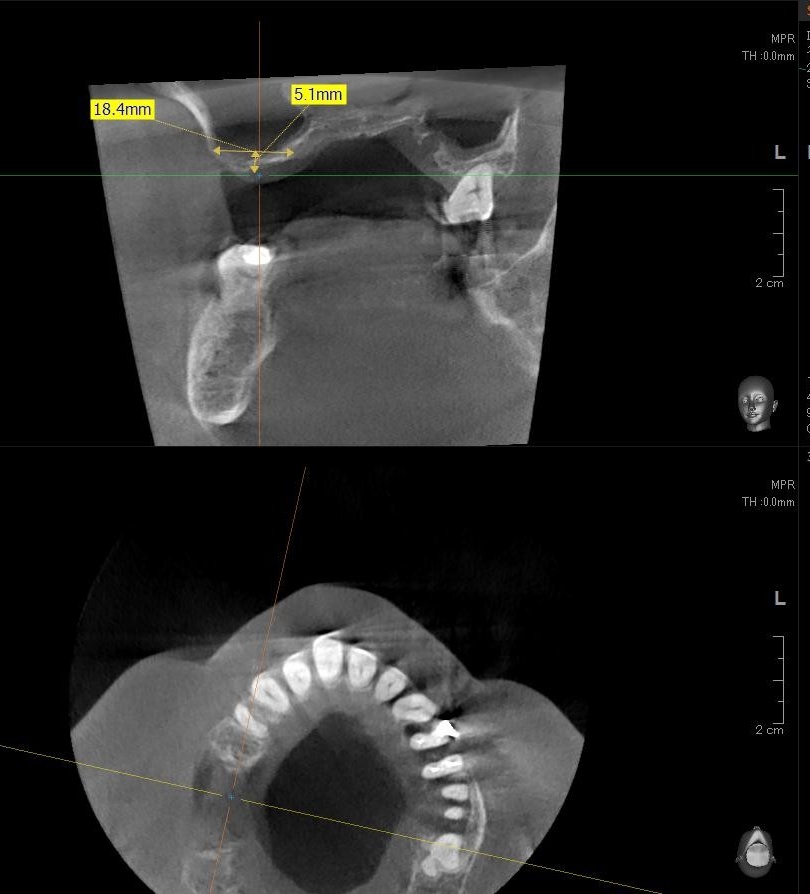

今回の患者様はインプラント植立を希望され、右上5番目・6番目・7番目の3本の植立が決まりました。

ドリルの先端を細い物から徐々に大きい物に変えながら、植立するインプラント体のネジの部分を除いた胴の部分の太さに合わせた大きさの穴を開けていきます。

開けた穴に、専用道具を使ってネジを締めるように長さ2センチ程のインプラントを骨に埋め込んでいきます。